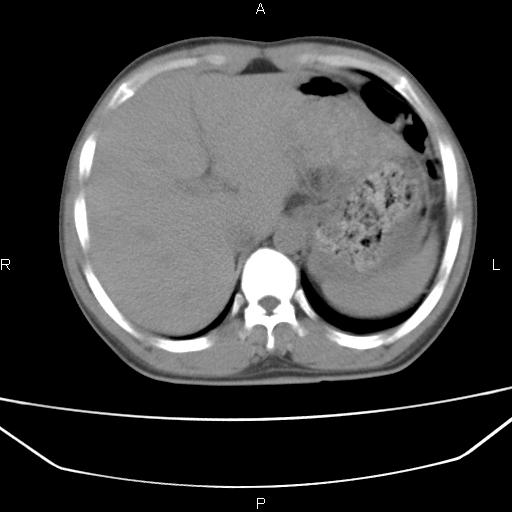

患者,男,40岁。间断发热,咳嗽二十余日。体温最高达38.9° 在当地诊所抗炎治疗三天后体温降至正常,患者自行停药。今又发热。胸片示,左下肺阴影。

左下肺片状高密度影,境界模糊,密度不均,考虑感染性病变可能性大,建议抗炎治疗后复查。左肺门增大,不除外占位性病变,必要时支气管镜检。